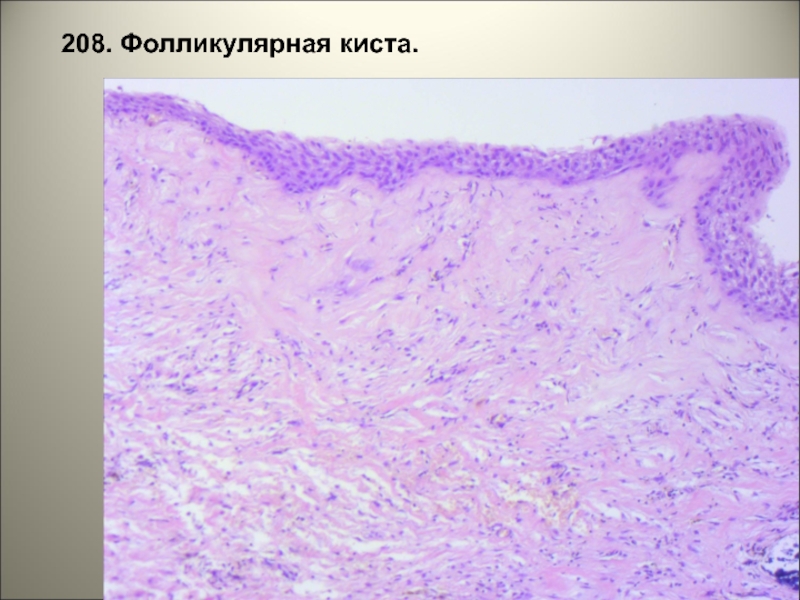

Гистологические изображения фолликулярной кисты яичника